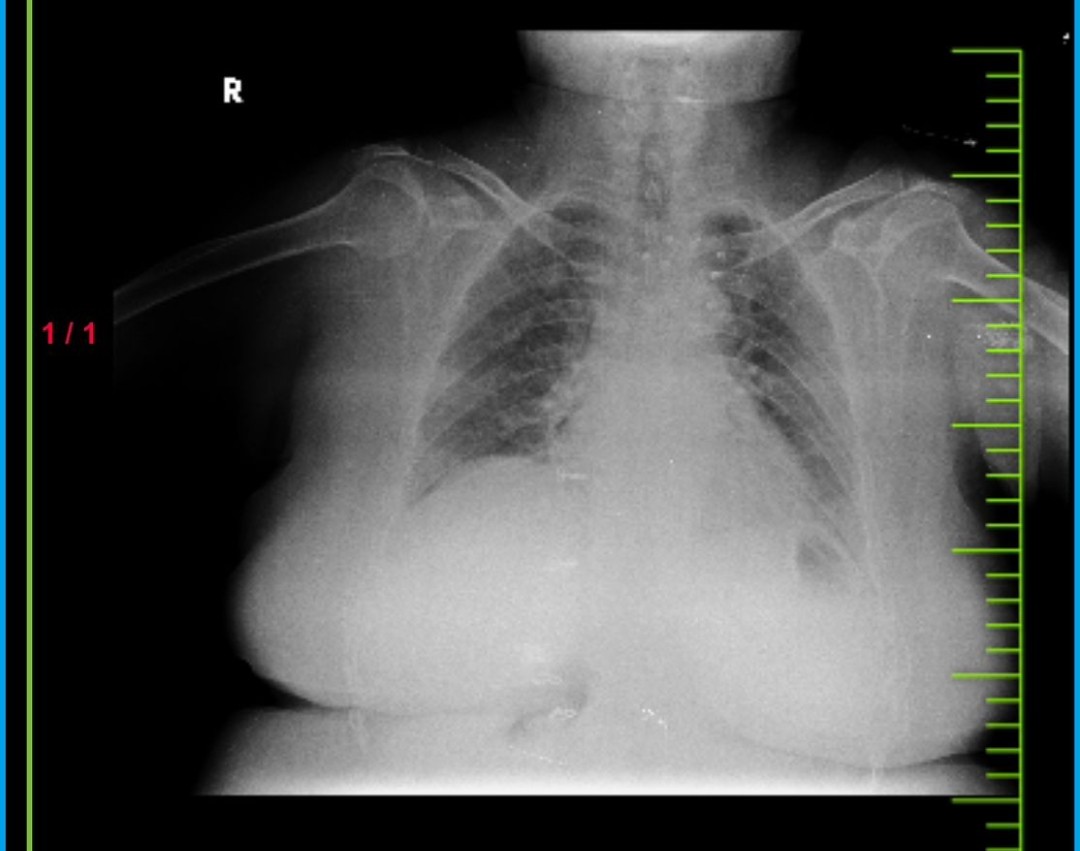

PPM 1 - Can you use your medical expertise to diagnose this x-ray? Also @PPM6.

PPM 1 - πStart counting the vertebrae from L5 which is just above the sacrum and then see the size of each vertebrae till you reach L2 and L1.

PPM 4 - Spondylolisthesis?

PPM 6 - Lumbar Spondylosis with Intervertebral Disc Degeneration.

lumbosacral region of the spine, which includes the lumbar vertebrae (L1 to L5) and potentially part of the sacrum (S1). This area supports much of the upper body's weight and is a common site for degenerative changes like disc degeneration and spondylosis.

PPM 7 - Collapsed vertebra.

Why don't you look carefully at the size of each lumbar vertebrae?

PPM 1 -No few days, Look carefully at the size of each lumbar vertebrae.

PPM 4 - Reduced size of lumbar vertebrae.

PPM 8 - Osteoporosis?

PPM 4 - Osteoporosis, Degenerative Disc Disease, Vertebral Compression Fractures, Aging. (Differentials from cgpt. I needed to take help)

For this patiet can rule out aging, can rule in possible influence of hormones causing osteoporosis.

Degenerative Disc Disease - unable to identify any reduction in space between vertebrae. Probably rule out.

Collapsed / fractured because of osteoporosis.

PPM 1 - Yes vertebral fractures present as a wedge shaped collapse.

PPM 1 - Even the size of the second and third appears reduced.